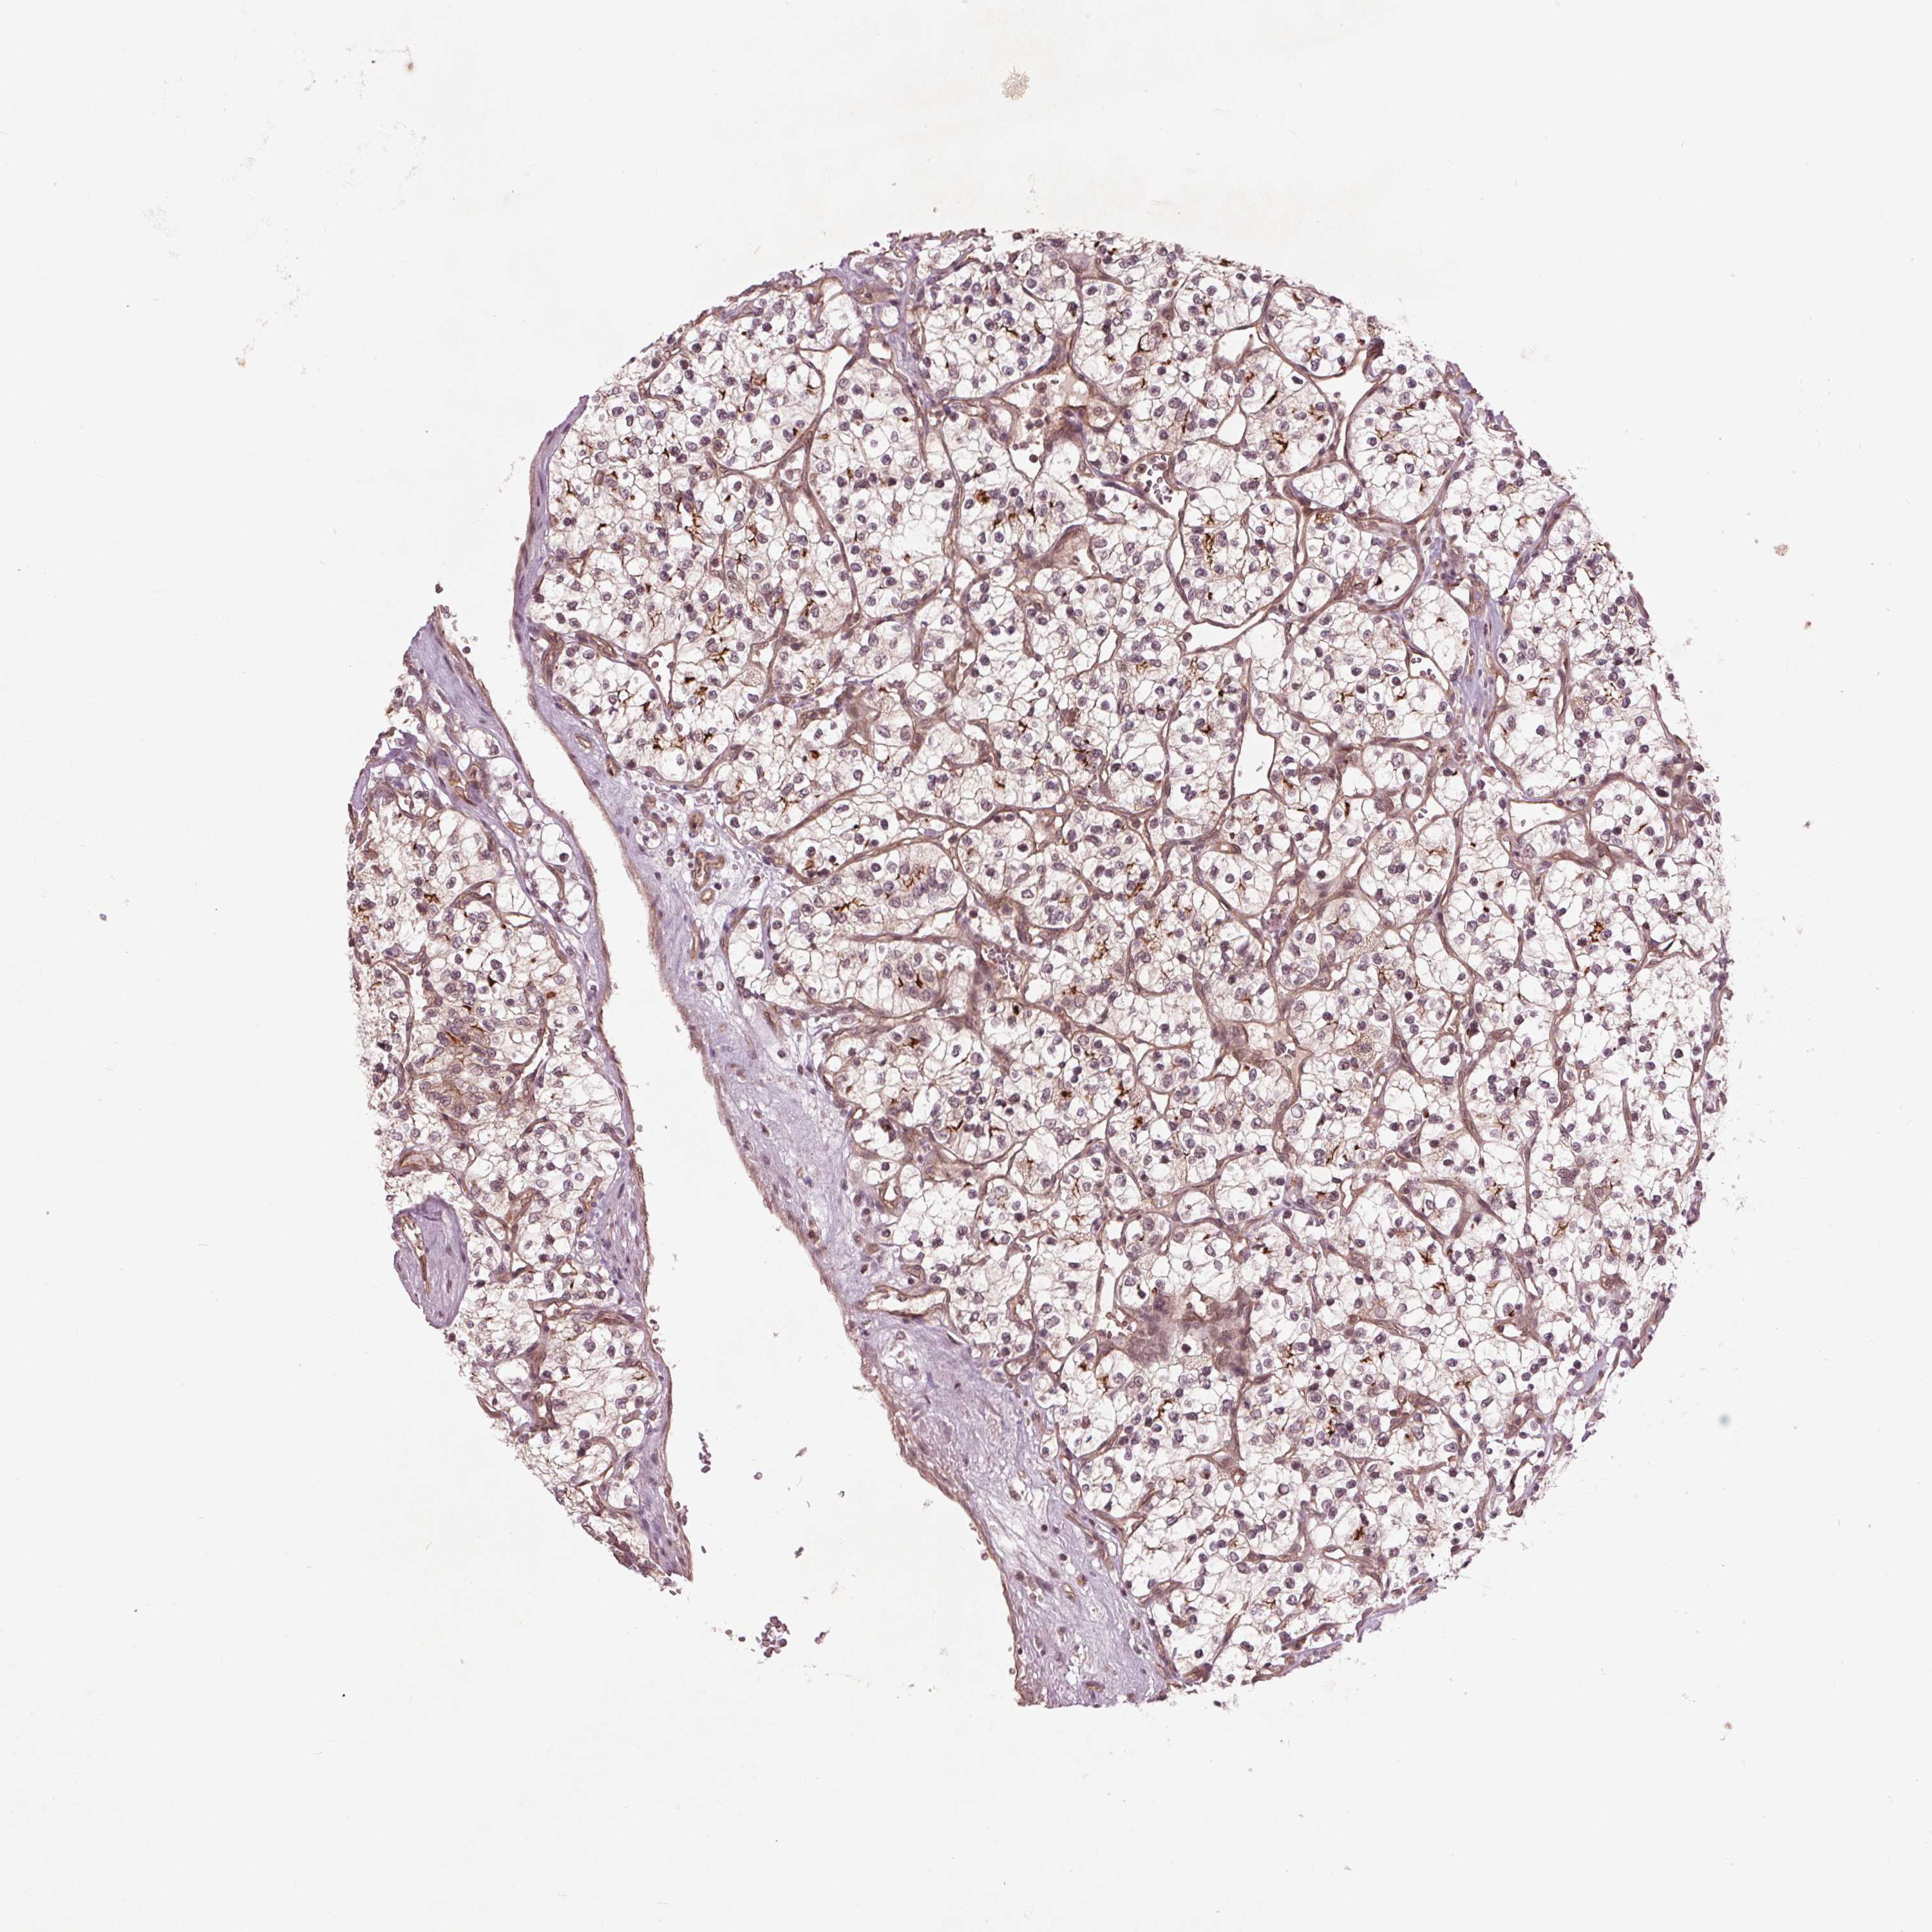

KIDNEY RENAL CLEAR CELL CARCINOMA (VALIDATION) - Interactive survival scatter ploti

The Survival Scatter plot shows the clinical status (i.e. dead or alive) for all individuals in the patient cohort, based on the same data that underlies the corresponding Kaplan-Meier plots. Patients that are alive at last time for follow-up are shown in blue and patients who have died during the study are shown in red.

The x-axis shows the expression levels (FPKM) of the investigated gene in the tumor tissue at the time of diagnosis. The y-axis shows the follow-up time after diagnosis (years). Both axes are complimented with kernel density curves demonstrating the data density over the axes. The top density plot shows the expression levels (FPKM) distribution among dead (red) and alive patients (blue). The right density plot shows the data density of the survived years of dead patients with high and low expression levels respectively, stratified using the cutoff indicated by the vertical dashed line through the Survival Scatter plot. This cutoff is automatically defined based on the FPKM cutoff that minimizes the p-score. The cutoff can be changed by dragging the vertical line or by entering a cutoff value in the square labeled "Current cut-off".

Under the Survival Scatter plot the p-score landscape (black curve; left axis) is shown together with dead median separation (red curve; right axis). Dead median separation is the difference in median mRNA expression between patients who have died with high and low expression, respectively. It is calculated as follows: median FPKM expression of dead patients with high expression - median FPKM expression of dead patients with low expression. This is intended to aid the user in visually exploring custom cutoffs and the associated p-scores and dead median separation.

Individual patient data is displayed and can be filtered by clicking on one or more of the category buttons on the top of the page. Categories describing expression level and patient information include: high, low, alive, dead, female, male and tumor stages. The scale of the x-axis can be toggled between linear and log-scale by clicking on the "x log" button. Mouse-over function shows TCGA ID, patient information and mRNA expression (FPKM) for each patient.

& Survival analysisi

Kaplan-Meier plots summarize results from analysis of correlation between mRNA expression level and patient survival. Patients were divided based on level of expression into one of the two groups "low" (under cut off) or "high" (over cut off). X-axis shows time for survival (years) and y-axis shows the probability of survival, where 1.0 corresponds to 100 percent.

BTBD1 is not prognostic in Kidney Renal Clear Cell Carcinoma (validation)

: 49.94

Average pTPM 44.7

Number of samples 100